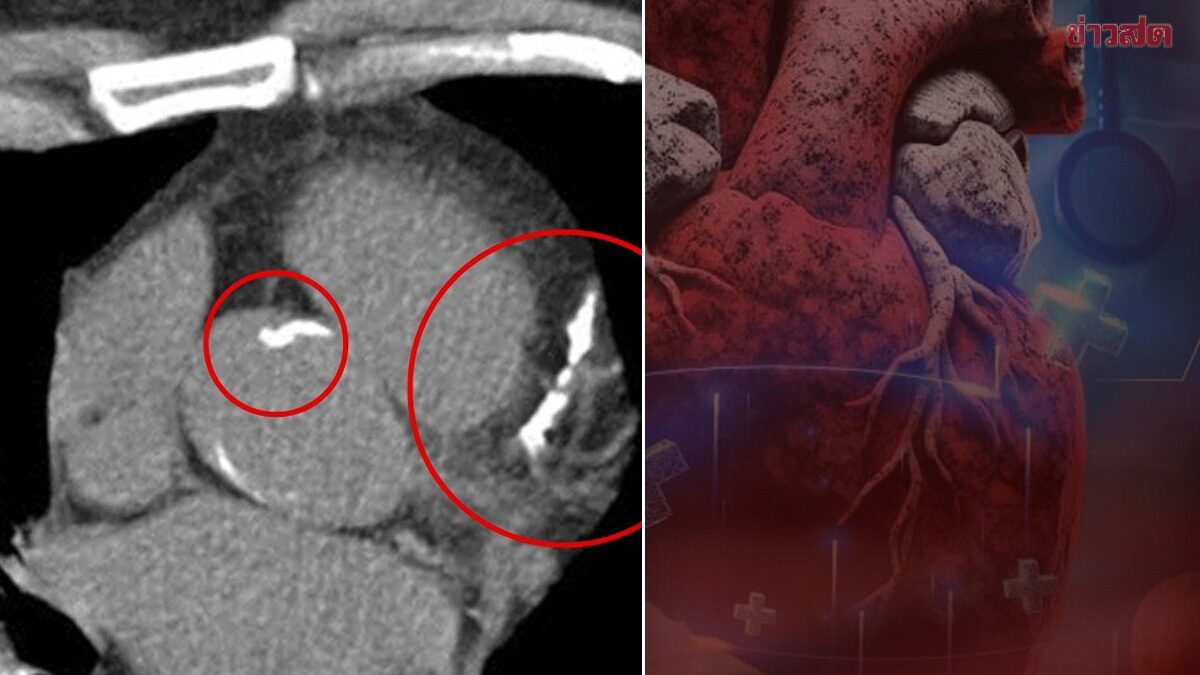

หมอเจด เผย 5 สัญญาณเตือน หินปูนเกาะหลอดเลือดหัวใจ มีอะไรบ้าง ระบุ สามารถสะสมเงียบ ๆ เป็นสิบปีโดยไม่เจ็บหน้าอก แนะ ควรตรวจตอนไหน เปิด 5 ข้อลดเสี่ยง วันที่ 6 มี.ค.2569 ผู้สื่อข่าวรายงานว่า นพ.เจษฎ์ บุณยวงศ์วิโรจน์ รองผู้อำนวยการโรงพยาบาลมหาราชนครราชสีมา โพสต์ภาพข้อความผ่านเพจเฟซบุ๊กชื่อ “หมอเจด” ระบุว่า อย่าพึ่งคิดว่าหลอดเลือดหัวใจตีบจะต้องมีอาการชัด ๆ ก่อนนะครับ เพราะความจริงแล้ว “คราบหินปูน” หรือแคลเซียมที่เกาะผนังหลอดเลือด สามารถสะสมเงียบ ๆ เป็นสิบปีโดยไม่เจ็บหน้าอกเลยครับ จนวันหนึ่งตีบมากพอหรือเกิดลิ่มเลือดอุดตัน กลายเป็นภาวะฉุกเฉินทันที โดยเฉพาะคนที่มีเบาหวาน ไขมันสูง สูบบุหรี่ หรือมีพุงลงพุง ต้องระวังให้มากครับ และนี่คือ 5 สัญญาณ หินปูนในเลือดเกาะหัวใจไม่รู้ตัวครับ 5 สัญญาณเตือน หินปูนเกาะหลอดเลือดหัวใจ 1.เหนื่อยง่ายกว่าปกติทั้งที่กิจกรรมเท่าเดิม เมื่อหลอดเลือดหัวใจเริ่มตีบ เลือดไปเลี้ยงกล้ามเนื้อหัวใจได้น้อยลง ทำให้หัวใจทำงานหนักขึ้น คุณอาจรู้สึกเหนื่อยง่าย เดินขึ้นบันไดแล้วต้องหยุดพัก ทั้งที่เมื่อก่อนทำได้สบาย […]